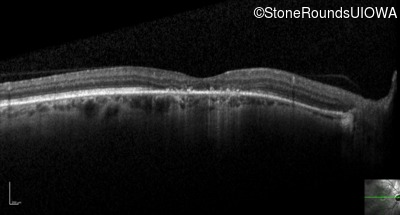

Optical Coherence Tomography - Left - 20/32 -1

Exemplar / OCT Stack

OCT Stack